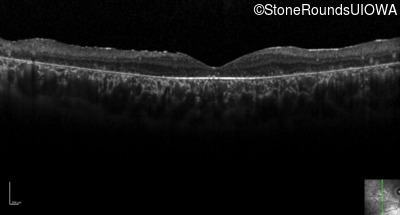

Optical Coherence Tomography - Left - 20/250 sc

Exemplar / OCT Stack